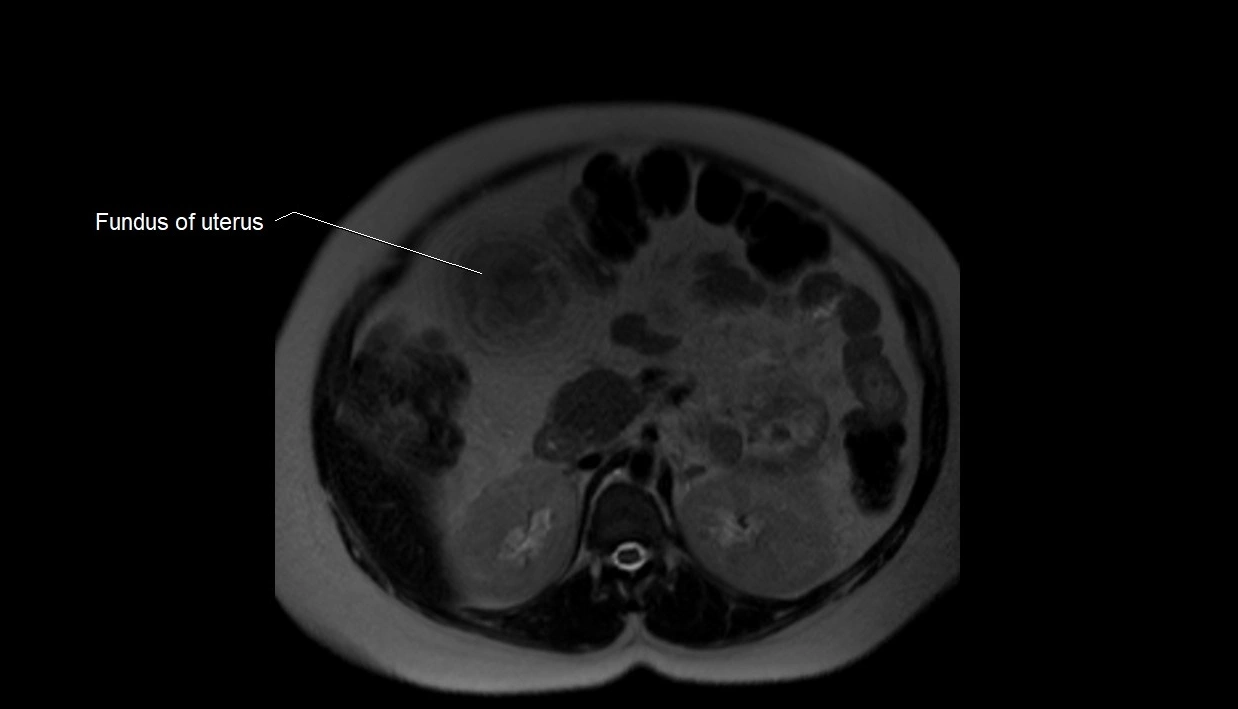

Amniotic fluid is the protective liquid surrounding the fetus within the amniotic sac. It plays an essential role in cushioning the fetus, enabling fetal movement, maintaining temperature stability, and allowing for normal lung and musculoskeletal development.

The volume and composition of amniotic fluid change throughout pregnancy. It is mainly derived from maternal plasma in early pregnancy, while in later stages, it consists largely of fetal urine, lung secretions, and transmembrane exchanges.

MRI Appearance

T2 HASTE (T2 GRE):

• Amniotic fluid shows very bright hyperintense signal

• Provides natural contrast against fetus and placenta